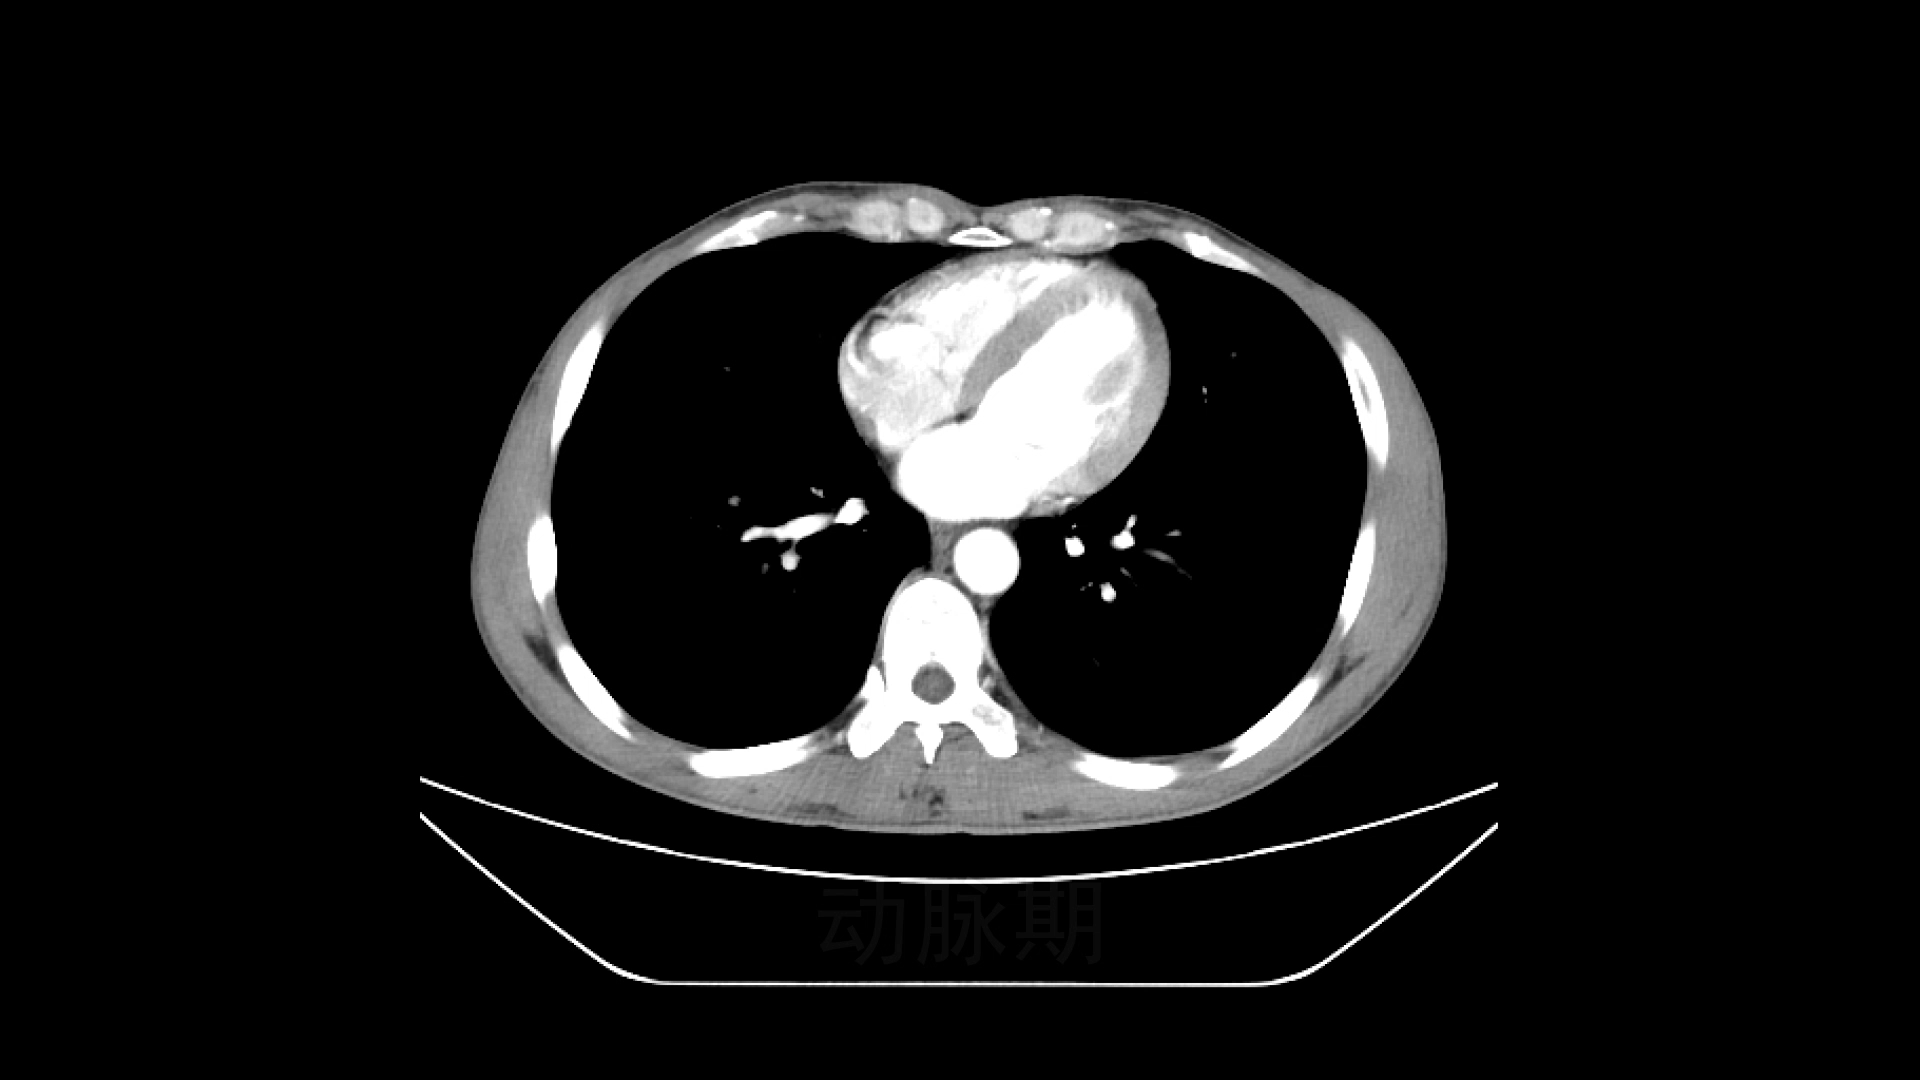

现病史:患者4月前不明原因出现左上腹痛,不伴乏力、纳差,无恶心、呕吐、腹痛、腹泻等不适,无发热、畏寒、咳嗽、咳痰等症状,患者遂至当地医院就诊,行腹部CT及EUS穿刺考虑胰腺神经内分泌肿瘤,建议手术治疗。患者考虑手术风险及进一步诊断,遂到我院门诊就诊。门诊以“胰腺体部占位:神经内分泌肿瘤”收住本科。自患病以来,精神、饮食较差,夜间休息可,大小便正常,体重4月内下降3kg。

【临床诊断】:胰腺占位:神经内分泌肿瘤